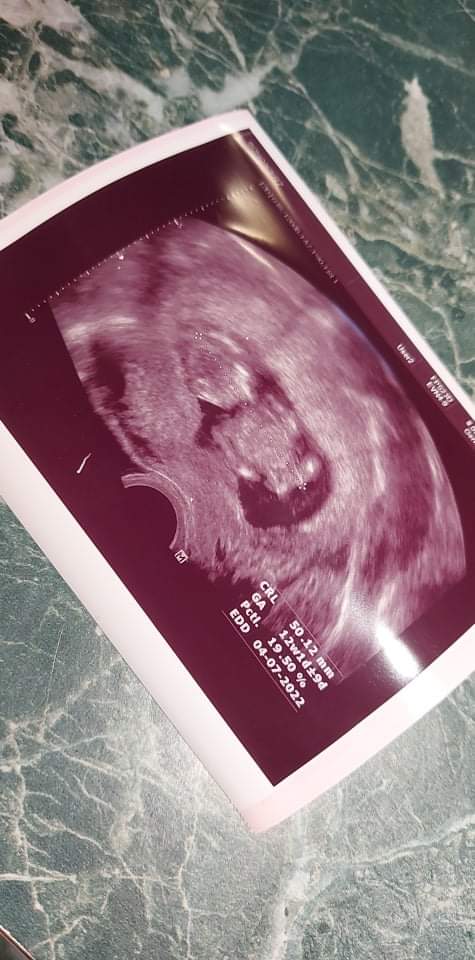

@fialka444 no prcek je akční 🤣jen sem řekla slovo fotka q bylo nemožné ho vyfotit 🤣🤣

@fialka444 dneska na UZ byl celkem v klidu ,i na krátkém videu co jsem natočila 🤣

@fialka444 ano už konečně na tom velkém screeningu předtím byl jen malý ultrazvuk a krev 🤣

Moc krásná fotečka🍀